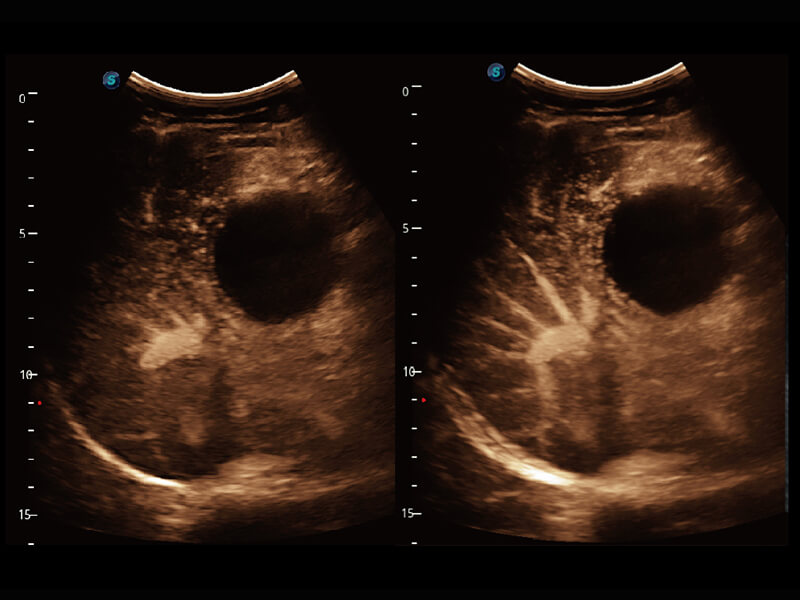

S60探头工艺,从前端信号处理每一个环节采集无损声学数据,真实还原组织原貌,再现解剖细节。

超宽频带技术,为容积成像带来优质的二维图像基础,为您呈现丰富的结构细节,栩栩如生地展示宝宝的宫内形态以及各种组织的立体结构。